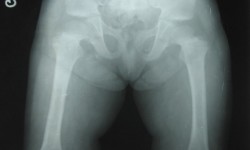

CHONDR ECTODERMAL DYSPLASIA (Ellis-Vancreveld syndrome)

By Admin | September 25, 2013 - 5:31 am | Musculoskeletal, Skeletal Dysplasias

Fig.4